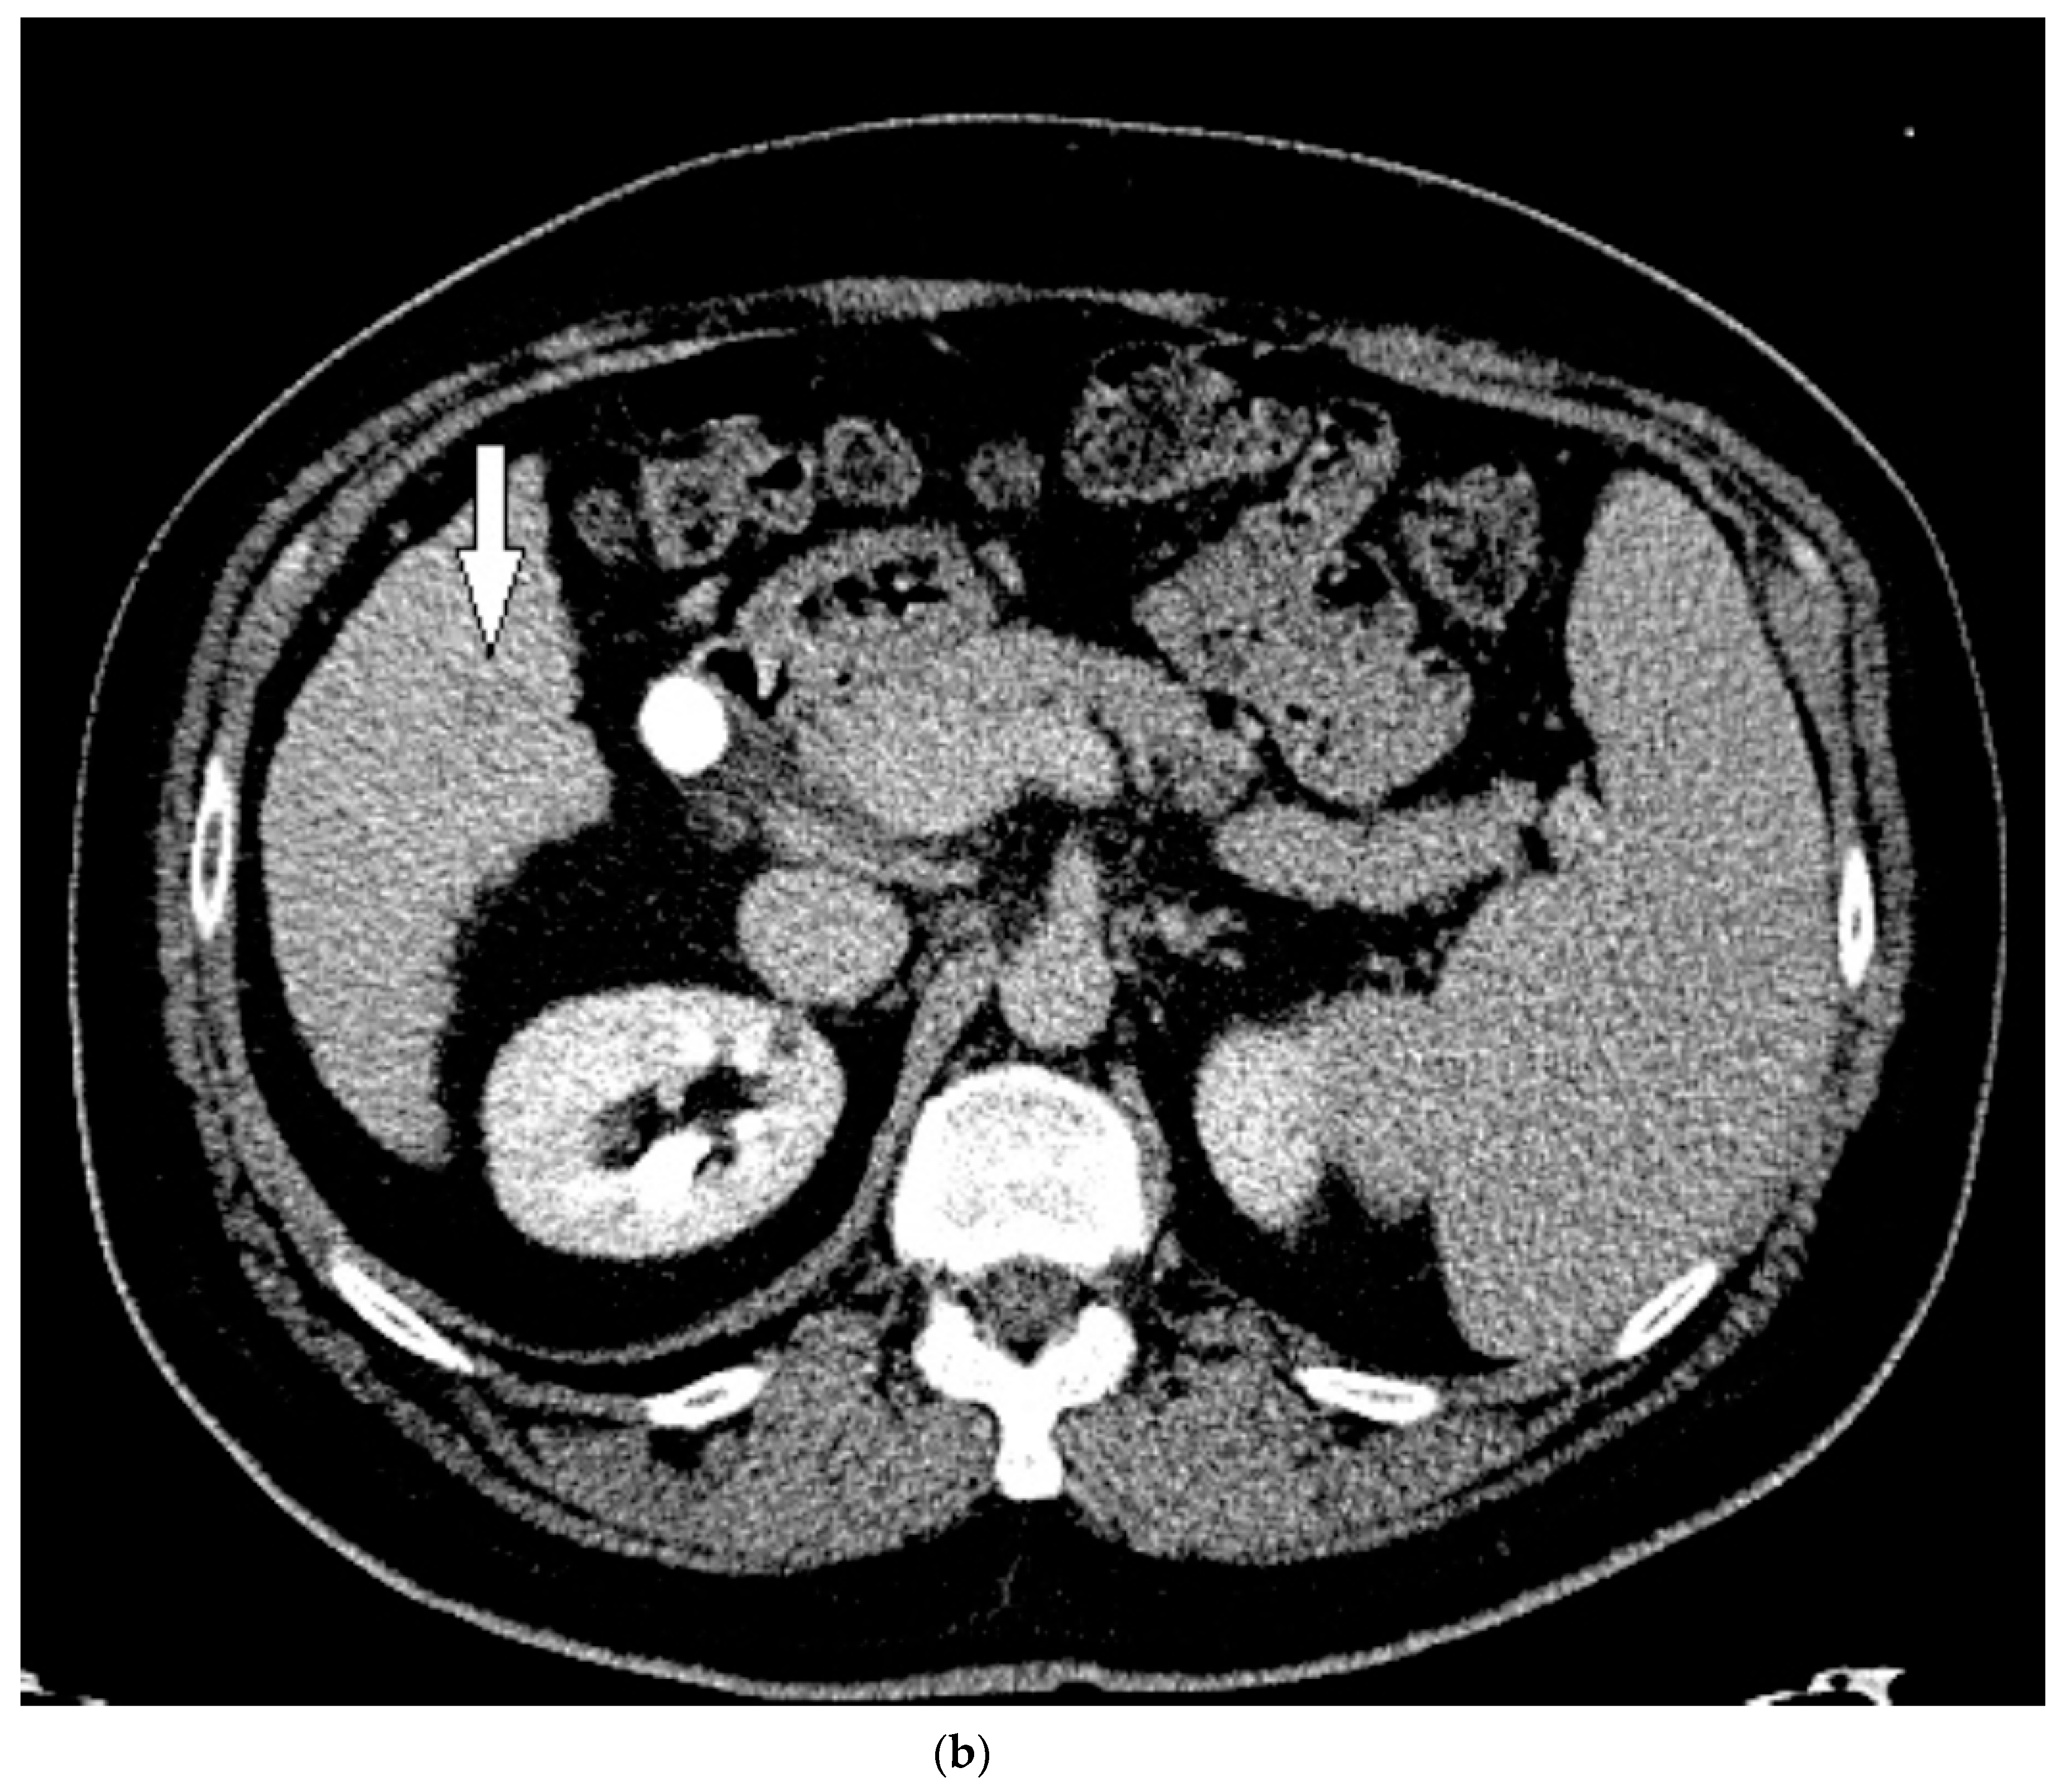

3.1. Case 1